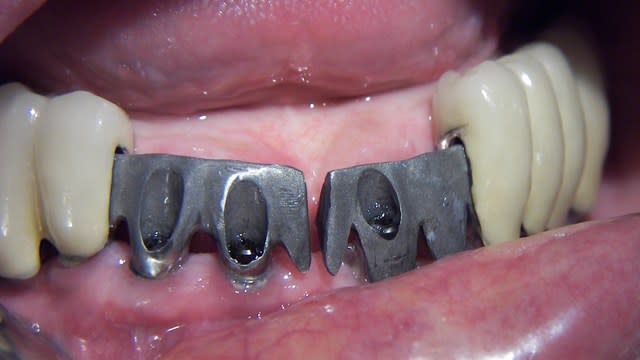

Bonsoir à tous je voudrais avoir votre avis sur ce cas :

8 implants maxillaires en vue d'une reconstitution fixe, je vous avoue que je pensais avoir pas trop mal placé au niveau axe (par rapport à certains de mes cas précédents ou la divergence était plus importante ) pourtant quand je veux verifier ma clef en platre pour valider mon empreinte, je ne parviens pas à insérer celle ci sans contraintes.

Sur le modèle en platre j ai le meme problème mais mon prothésiste me dit que çà vient de ma divergence d'axes implantaires

Ils sont vestibulés c'est sur mais cette orientation n'est elle pas naturelle du fait de la résorption maxillaire?

comment procédez vous ? Avez vous ce problème pour la clef ?

Par la suite je peux jouer sur les piliers pour améliorer mon parallélisme mais je voulais avant valider le modèle.